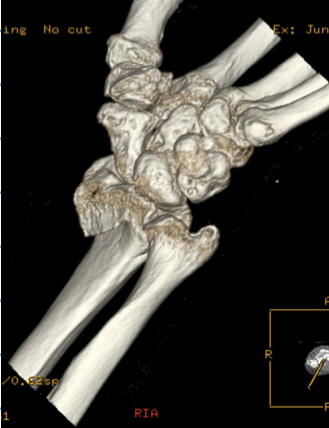

80列マルチスライス撮影により、撮影は約10秒程度です。また、被ばくに対し配慮した設計により、高感度のX線検出器を使用し、低線量、高画質の撮影で安心して検査を受けて頂く事が出来ます。

肩関節